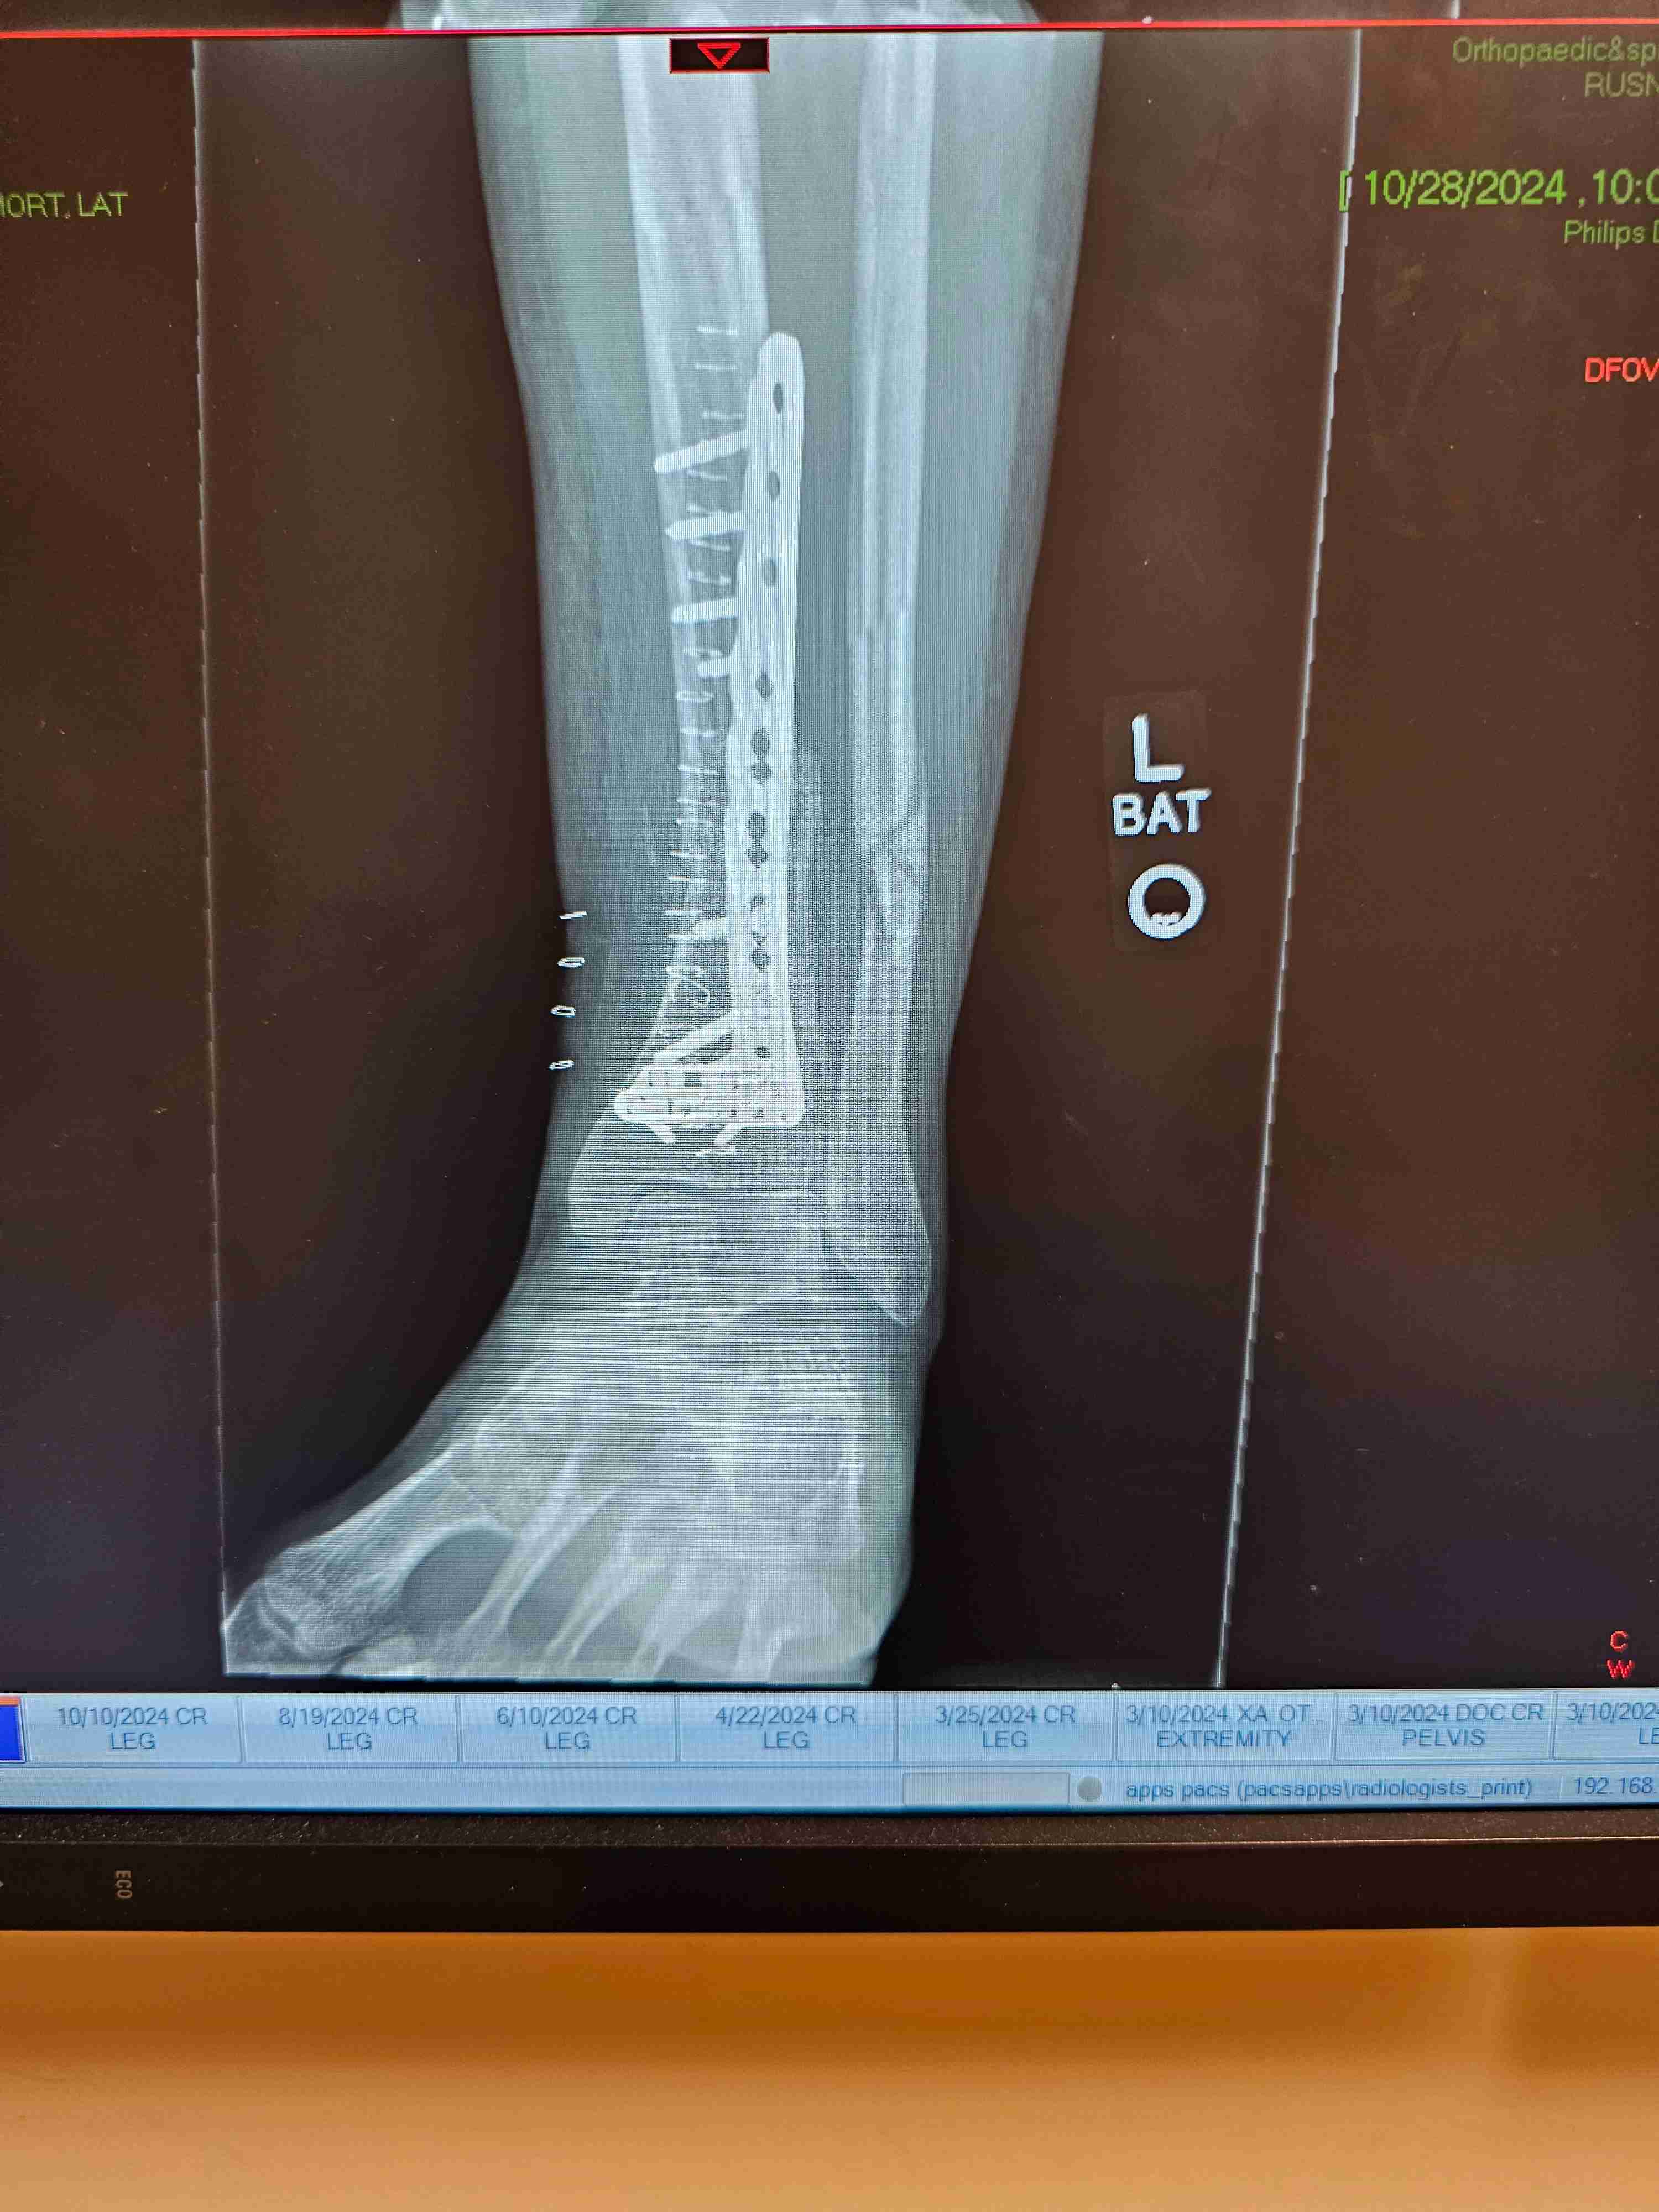

New here. Went through inpatient about 18 months ago. Things were going well. Was getting back into MTN sports. Then was hit from behind while snowboarding. My leg was broken badly. 2 surgeries. Had a bone graft about 2 months ago. Gunshy and depressed about getting out of bed and slowly back to work. Depressed yet restless. Urges are always on the back burner. Pretty shut down socially.

Missing the Phoenix. Healing slowly yet still can barely walk.

Daaang! That looks so painful. The phoenix has some virtual groups as well. I know that's not always as satisfying as physical activities but could be an option to connect. I like the music and art groups.